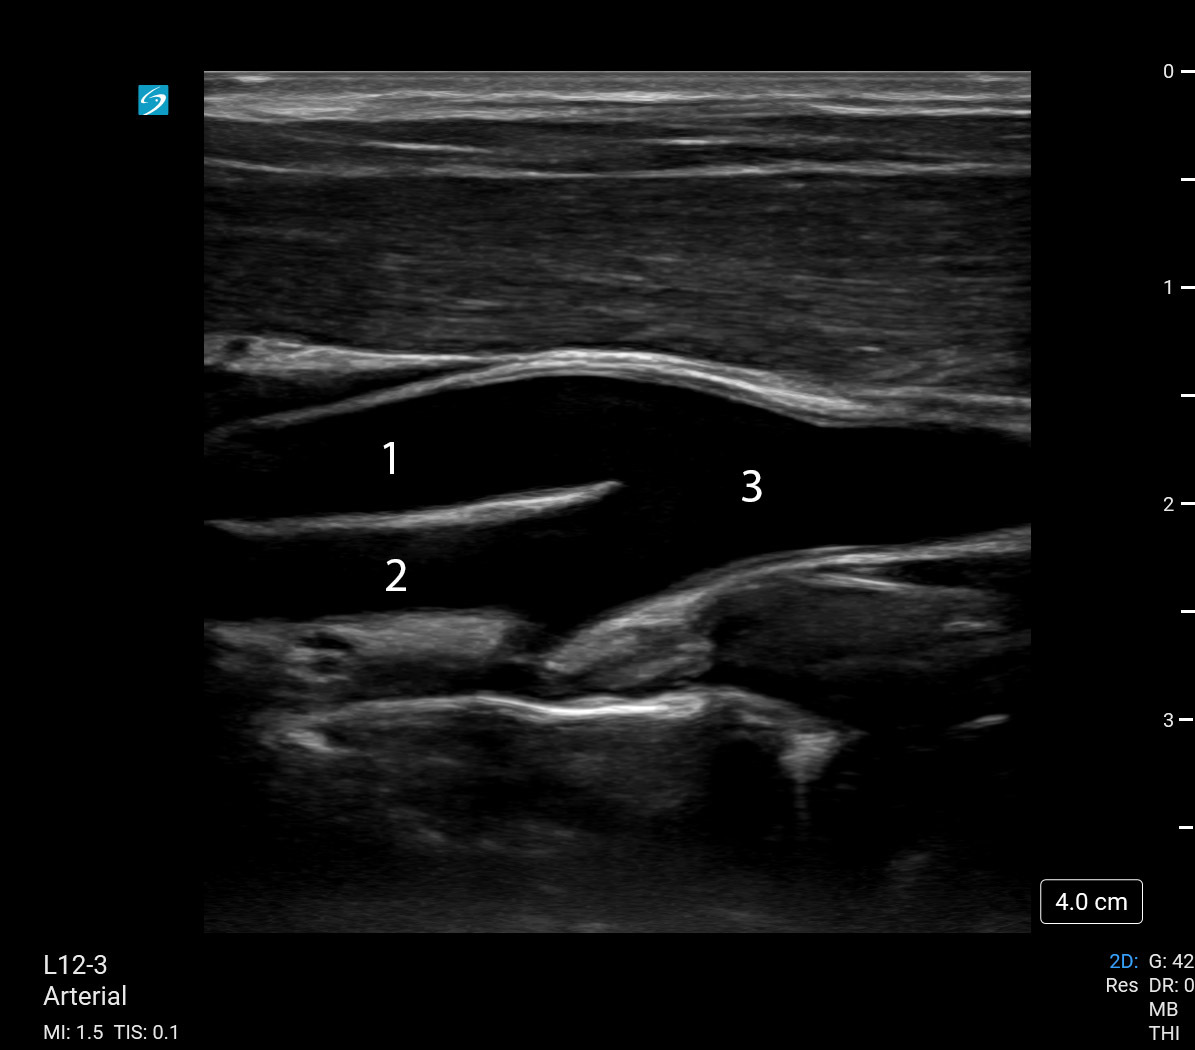

Bild: Verzweigung der Karotis

1. Arteria carotis externa (ACE)

2. Arteria carotis interna (ACI)

3. Arteria carotis communis (ACC)